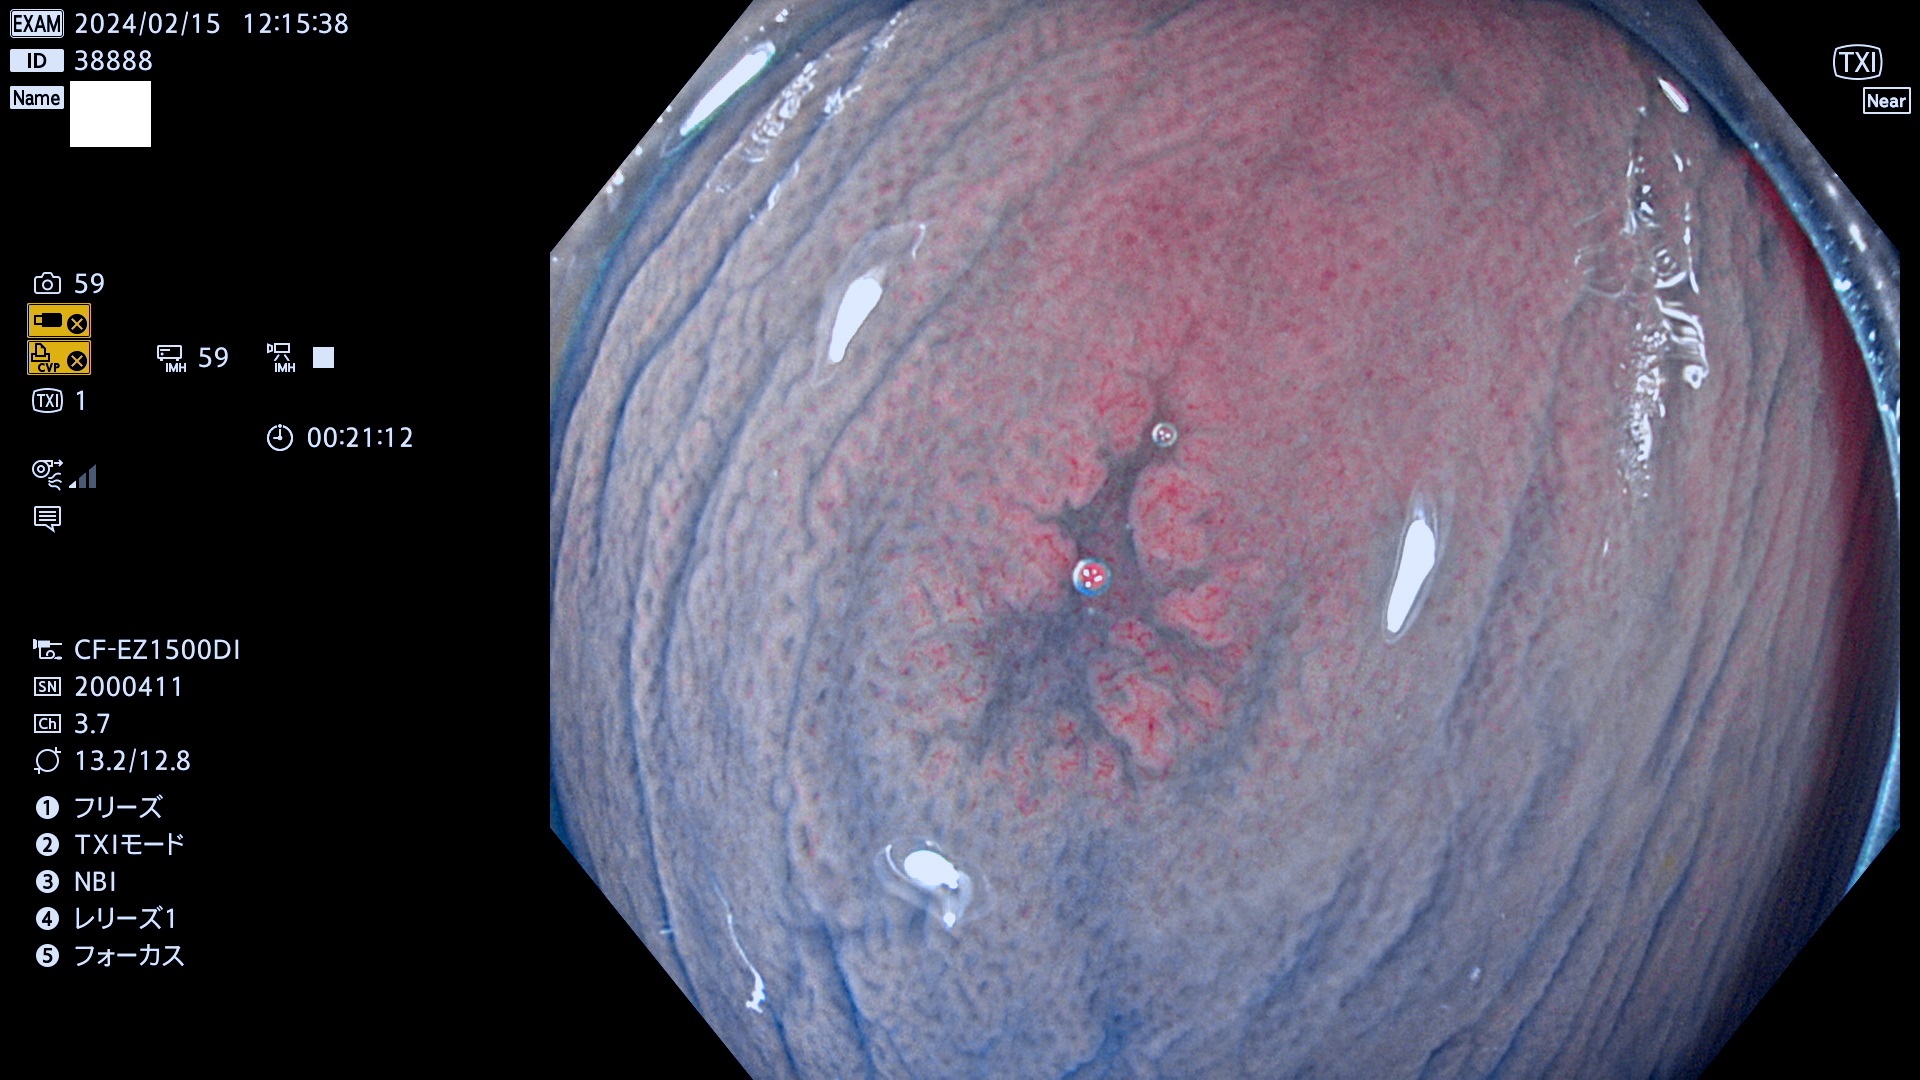

表面型腺腫(Flat Adenoma)の中で、完全に平坦な物をUb、陥凹している物をUcと呼びます。平坦隆起型(Ua)よりも、発見が難しく危険な病変です。

毎週の検査(木・金・土・日)に発見されたUb、Uc型・腺腫を、その週の日曜の夜にUPし1週間、提示します。

抽出の対象期間 2024年2月15日(木)〜2月18(日)の4日間(40件の検査)10件 (10/40=25%)